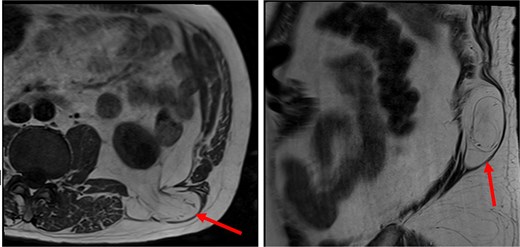

At follow-up, the patient was reviewed for consideration of lipoma excision. MR imaging confirmed that the abnormality thought to be a lipoma was in fact a superior lumbar hernia which contained retroperitoneal fat but no bowel or other visceral structure (Fig. 1). The neck of the hernia measured up to 20 mm.

The patient’s MR imaging, which clearly shows the superior lumbar hernia. Axial section (left), sagittal section (right).